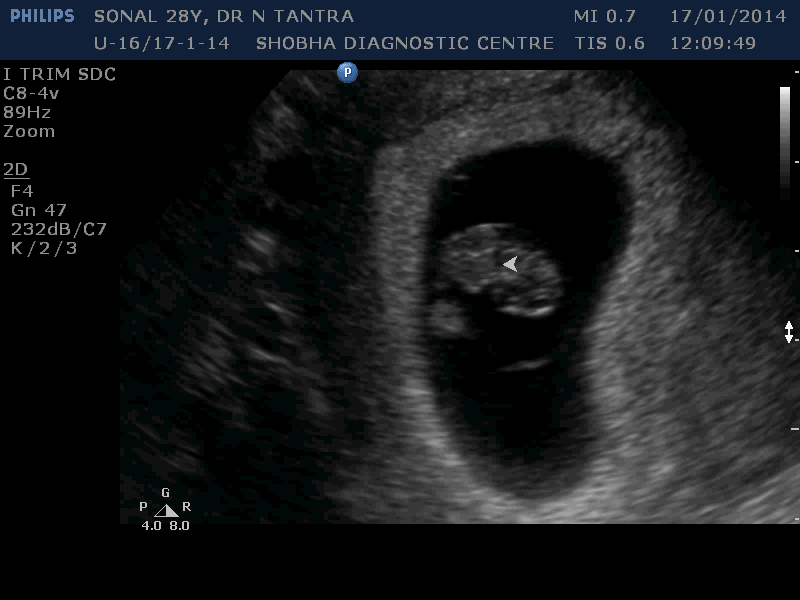

Early Sonography

Before 10 weeks

- It tells you the exact duration of pregnancy.

- It rules out pregnancy lying outside the uterus at early stage to safeguard your life.

- It tells you whether it is single or multiple pregnancies (Twins / Triplets).

For this, Sonography is done vaginally (internal examination).